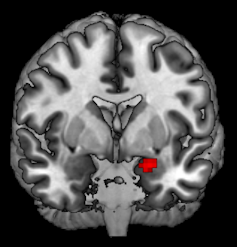

There are two major regions in what brain scientists call the “offspring care neural network,” evolutionarily old structures deep in the brain called the amygdala and the periaqueductal gray.

The amygdala is a small almond-shaped structure in both hemispheres tucked below the cortex. (Amygdala means almond in Greek.) One of its main roles in the brain is picking up on important emotional cues.

We found some interesting effects while reviewing images captured during this experiment. Most notably, the amygdalas and their periaqueductal gray were more active for kidney donors than people in our control group, with stronger reactions to fearful and distressed stimuli.

What we found suggests that these two regions might be communicating or otherwise working together. We further tested this finding by looking at another aspect of our brain scans that allowed us to analyze how these two regions are connected by nerve cells.

My colleague Katherine O'Connell, a doctoral student, found that there seemed to be greater structural connections between these two regions too. These connections may help nerve impulses travel between them.